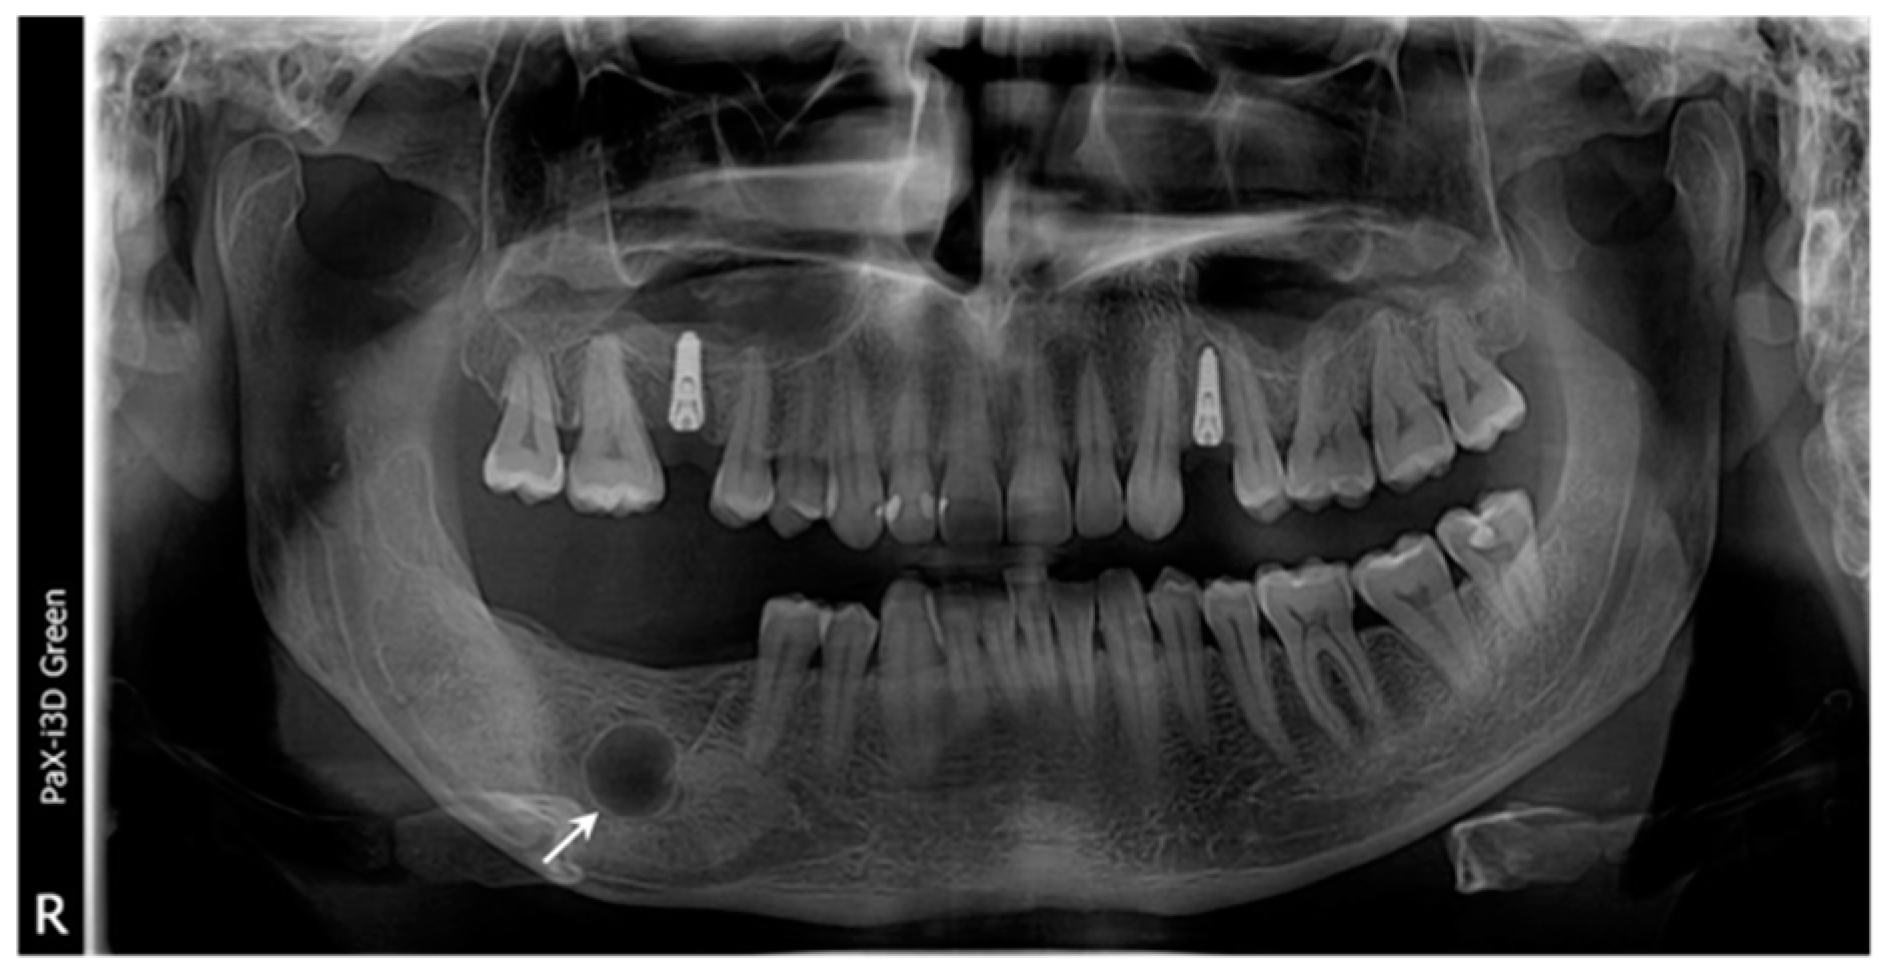

2. Case Presentation